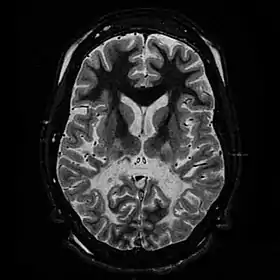

عندما يحدث ضرر للمادة البيضاء، يمكن أن تؤدي الاستجابات المناعية إلى التهاب في الجهاز العصبي المركزي (CNS)، إلى جانب فقدان المايلين. يمكن ملاحظة انحطاط المادة البيضاء في فحص التصوير بالرنين المغناطيسي واستخدامها لتشخيص الكريات البيض. تتميز حثل المادة البيضاء بأعراض محددة، بما في ذلك مشاكل التوازن والحركة، واضطراب السيطرة على العضلات، مشاكل السمع والكلام والرؤية في نهاية المطاف. على الرغم من أن هذا المرض قاتل، فإن عمر ظهور المرض هو عامل رئيسي حيث يتم إعطاء الأطفال عمرًا يتراوح من 2 إلى 8 سنوات (أحيانًا أطول)، في حين أن البالغين عادةً ما يعيشون أكثر من عقد بعد ظهوره. خيارات العلاج محدودة، على الرغم من أن زرع الخلايا الجذعية المكونة للدم باستخدام النخاع العظمي أو دم الحبل السري كما أنه يساعد في أنواع معينة أثناء إجراء مزيد من البحوث.